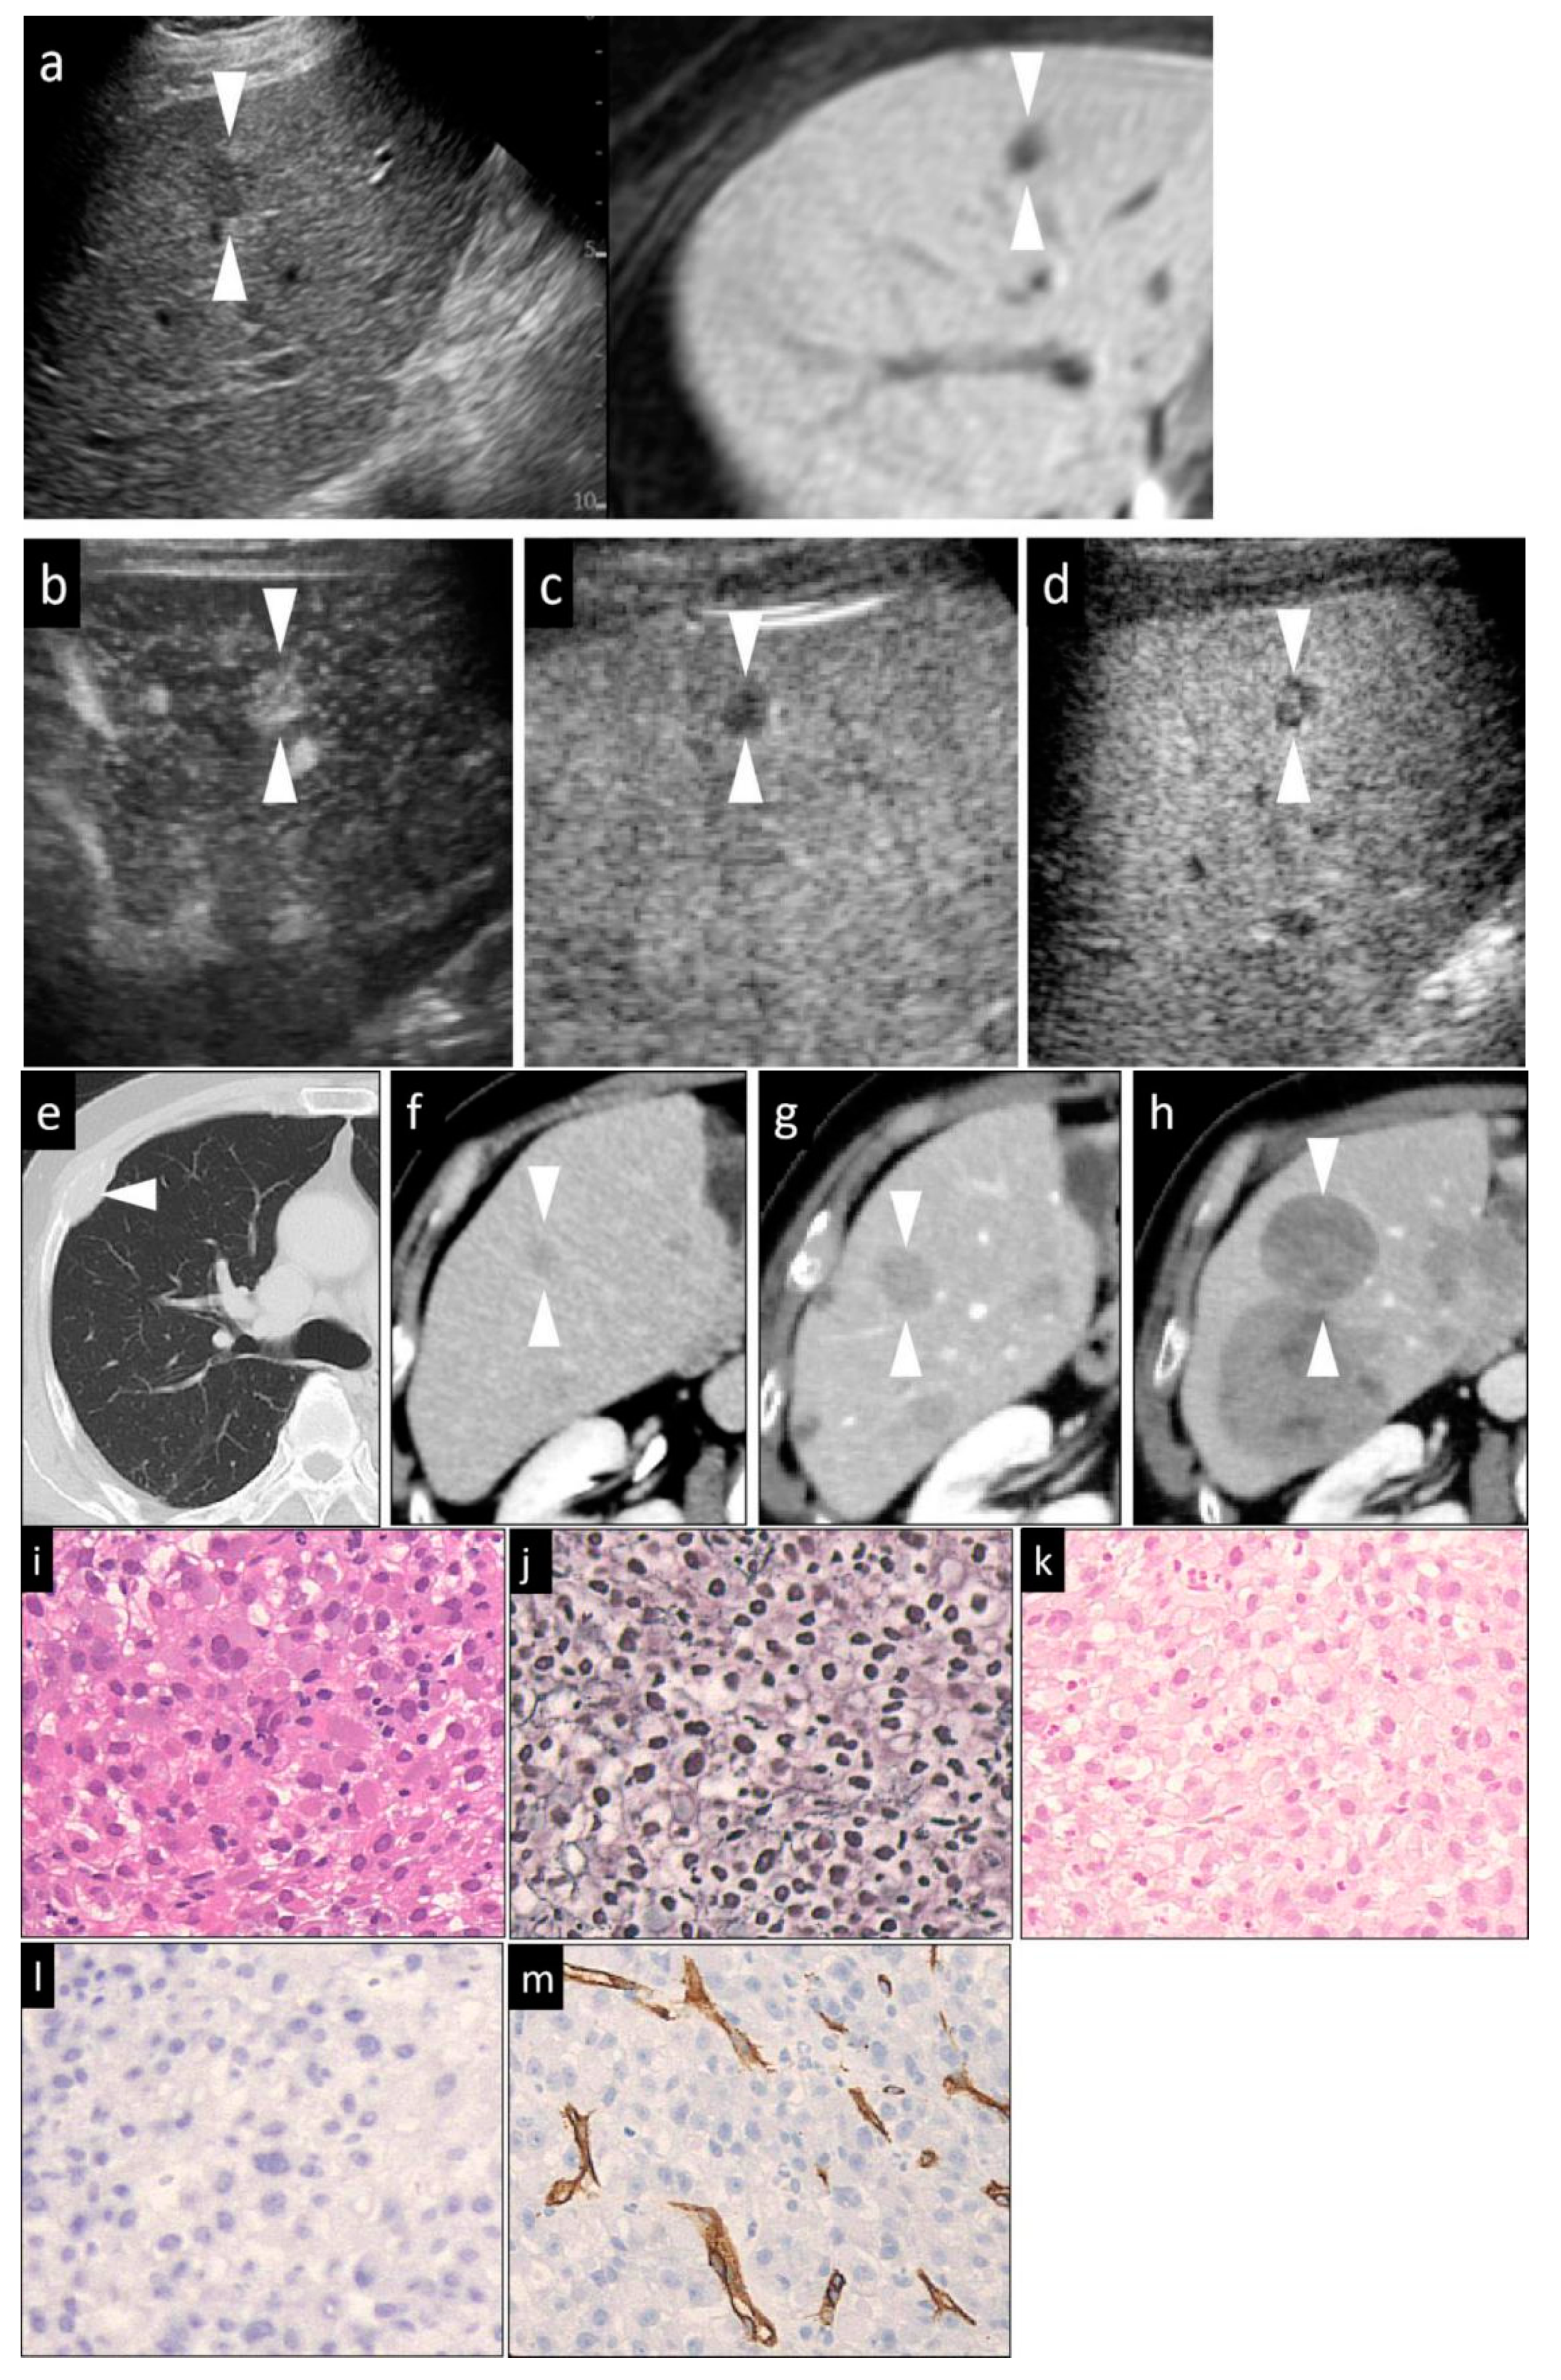

| Histological differentiation grade | Early HCC | Slightly enlarged, non-spherical nuclei; Mild hyper-cellularity; slight increase of the N/C ratio | Normal or clear thin trabeculae | Clear and evenly distributed | Negative or focal | Presence | Decrease or absence | |

| Advanced HCC | Well-differentiated | Large, irregularly shaped of nucleus; hypercellularity; increased N/C ratio | Thick trabeculae | Clear and recognizable | Diffuse | Absence | Absence | |

| Moderately differentiated | Markedly enlarged, deformed nuclei; hypercellularity; increased N/C ration; multinucleated giant cells (occasionally seen) | Thick trabeculae or solid structures | Sometimes unclear and sparse | Diffuse | Absence | Absence | ||

| Poorly differentiated | Large, bizarre-shaped nuclei; marked increase of the N/C ratio; multinucleated giant cells (frequently seen) | Disappeared trabecular and solid structure | Disappear | Diffuse | Absence | Absence | ||